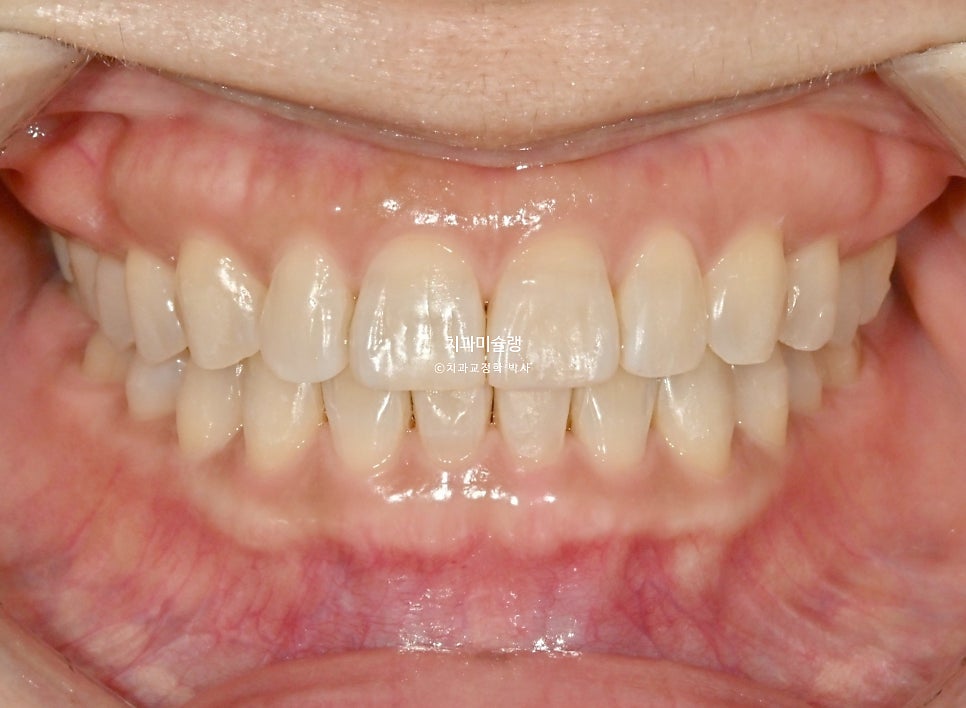

이제 전후비교 보겠습니다. 총 치료기간은 7개월, 재제작은 1회 했습니다.

치료 결과 비교

과개교합과 중심선은 개선되었으며

액간 뻗쳐있던 앞니 각도도 깔끔해졌습니다.

미소가 귀여우신 환자분. 깔끔해진 스마일라인이 돋보이네요.